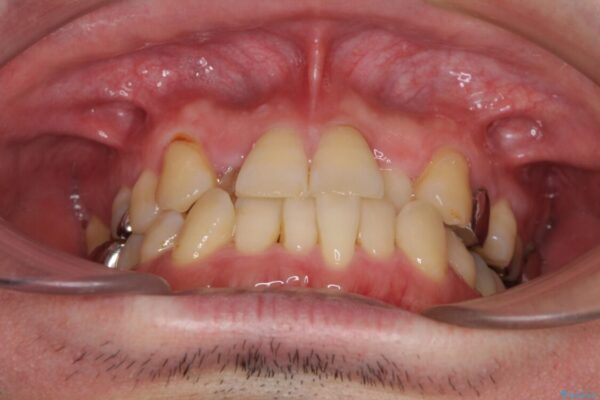

奥歯の痛みと前歯のデコボコを気にして来院された患者様です。

左右下顎の大臼歯は、ともに歯根が破折しており、抜歯が必要な状態でした。

放置したことで炎症による骨吸収が顕著であるため、骨造成を併用してインプラント埋入を行うこととしました。

咬み合わせは受け口傾向であり、上顎前歯の叢生が顕著であったことから、第1小臼歯抜歯による矯正治療も検討しましたが、下顎大臼歯を左右ともに抜歯するため、非抜歯による矯正治療を行うこととしました。

治療前

• 割れてしまった奥歯とデコボコの前歯 矯正治療とインプラント治療 治療前画像